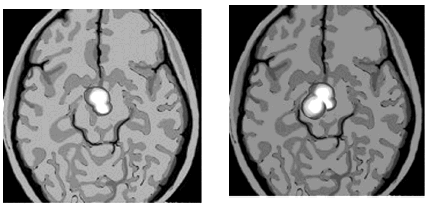

Ниже показаны результаты сканирования мозга «безумно влюбленного» человека и кокаинового наркомана. Убедитесь, что они почти идентичны.

На левом снимке показан участок мозга, активизирующийся у «безумно влюбленного» человека. На правом снимке показан участок мозга, который активизируется при употреблении кокаина

Итак, влюблены ли вы или просто приняли наркотик, ваши ощущения будут одинаковыми. Сканирование также показывает, что у матерей, которые смотрят на своих младенцев, проявляется та же мозговая активность, что и у людей, глядящих на своих любимых. Бартельс и Зеки сделали вывод о том, что романтическая и материнская любовь связаны с продолжением рода, поскольку и любимый человек, и младенец обещают сохранение ДНК.